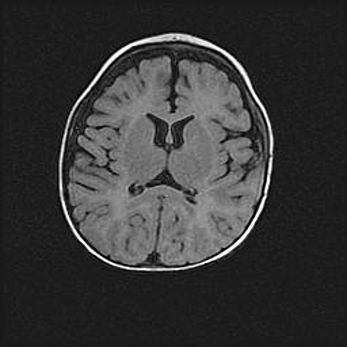

Церебральная ишемия II.

Возраст: 5 дней

Вес: 3400 г

Пол: женский

Окружность головы: 35 см

Срок гестации: 39 недель

Церебральная ишемия – это заболевание, характеризующееся недостаточностью (гипоксией) либо полным прекращением (аноксией) снабжения мозга кислородом по причине закупорки одного или нескольких сосудов. Это приводит к  что метаболическим расстройствам различной степени тяжести в тканях головного мозга, развитию коагуляционных некрозов и гибели нейронов.